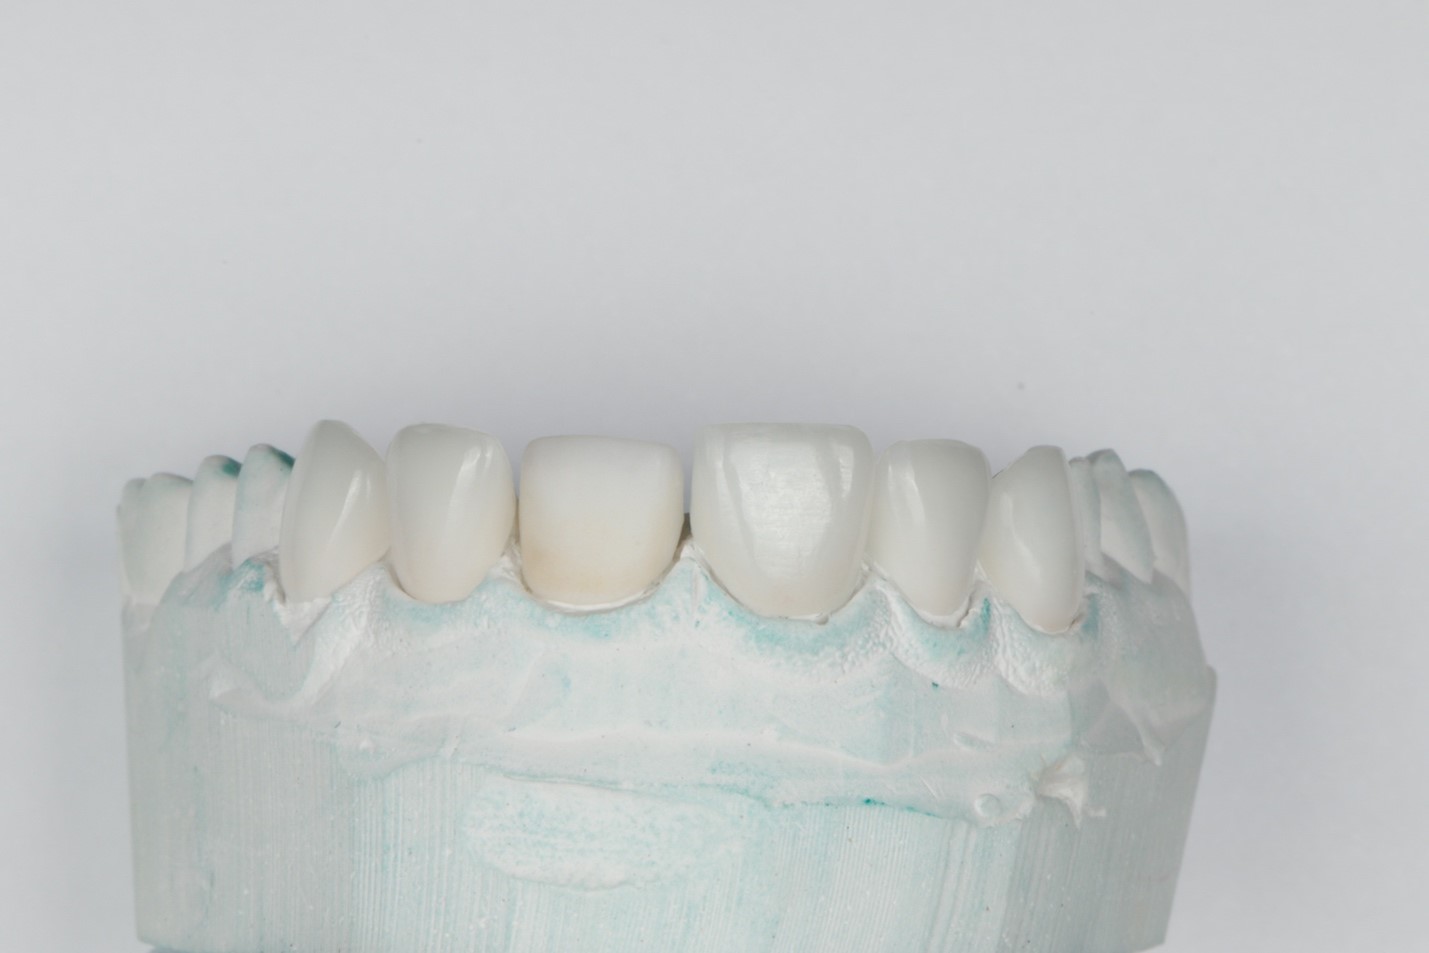

После определения цвета, был изготовлен колпачок IPS E.max Press (Ivoclar Vivadent) из таблетки цвета МО-2. После припасовки колпачка на контрольной гипсовой модели (Рисунок 5) и согласовании его с врачом были изготовлены керамические виниры Noritake EX-3, (Kuraray Noritake Dental Inc., Япония) однородной толщины и структуры (Рисунок 6). После проверки виниров на контрольной модели работа была направлена в клинику для припасовки и фиксации.

Рисунок 5. Керамические виниры и колпачок на зуб 21.

Рис. 6. Керамические виниры на рабочей модели.